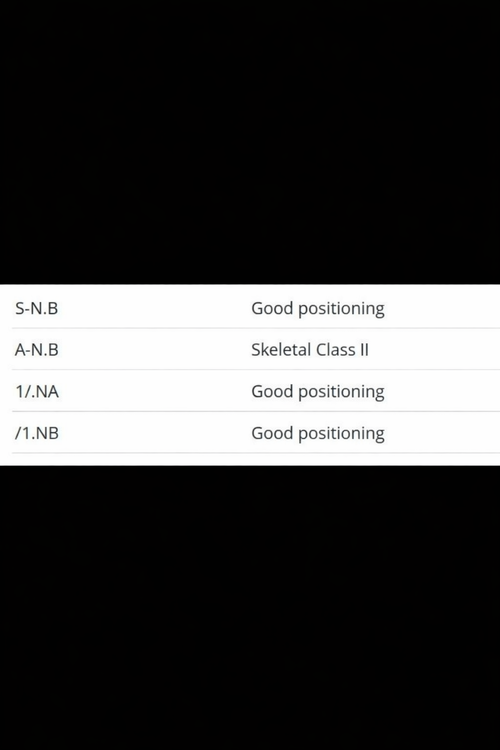

I also feel like my lower teeth are more inward (I’m not sure how to explain it exactly). I’d like to know the best way to fix this. I’ll send some photos and my cephalometric analysis, If you could please use simpler English, I would appreciate it, as I am Brazilian and it's difficult to translate(Note: I also feel a slight muscular difference when touching my face.)

I also feel like my lower teeth are more inward (I’m not sure how to explain it exactly). I’d like to know the best way to fix this. I’ll send some photos and my cephalometric analysis, If you could please use simpler English, I would appreciate it, as I am Brazilian and it's difficult to translate(Note: I also feel a slight muscular difference when touching my face.)

Attachments

Screenshot_20260403_195001_ChatGPT.jpg193.5 KB · Views: 0

Screenshot_20260403_195001_ChatGPT.jpg193.5 KB · Views: 0 -